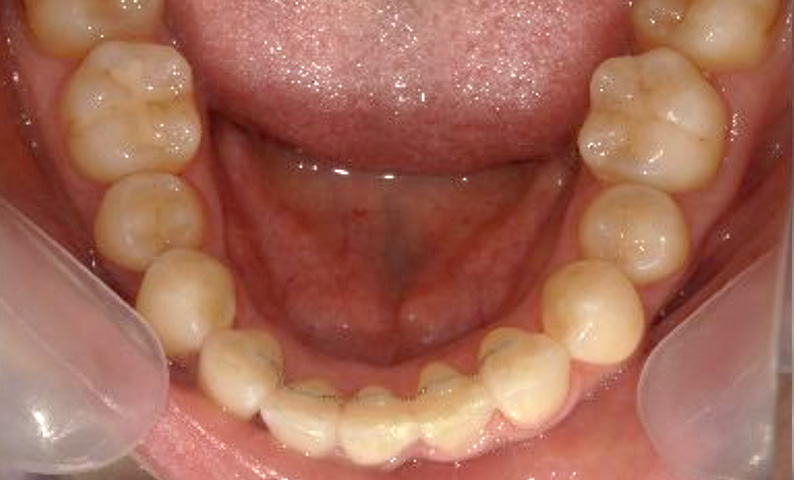

症例_001 下顎だけの部分矯正

治療期間:8ヶ月金額:21万円+税女性前歯のガタガタ下の前歯だけ

| Before | After |

|---|---|

|